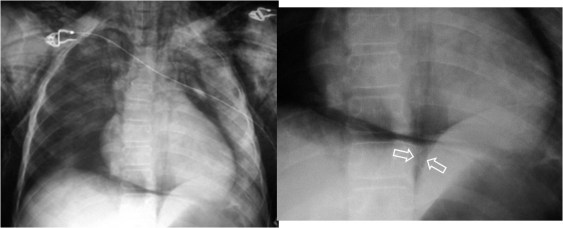

Las flechas señalan la pleura despegada del mediastino.

La presencia de neumomediastino provoca el despegamiento lateral de las dos hojas pleurales. En la radiografía PA de tórax esta imagen es más fácilmente visible en el margen izquierdo de la silueta cardiomediastínica. La pleura despegada es visible como una línea radioopaca que tiene un recorrido más o menos paralelo al contorno cardiomediastínico.

Radiografía AP de tórax en un paciente con traumatismo torácico. A la derecha las flechas marcan el signo de la V de Naclerio.

Signo de neumomediastino en la radiografía de frente de tórax. Corresponde a la presencia de aire mediatínico que ocupa la parte inferolateral del mediastino. El brazo medial de la V lo forma el aire que delimita la porción inferior del margen mediastínico izquierdo, mientras que el brazo lateral de la Vestá producido por el aire entre la pleura parietal y el hemidiafragma izquierdo.

En las fotografías vemos el signo en un paciente con traumatismo torácico que también presenta enfisema subcutáneo extenso (marcado en amarillo) y una contusión pulmonar en el lado izquierdo (flechas azules).